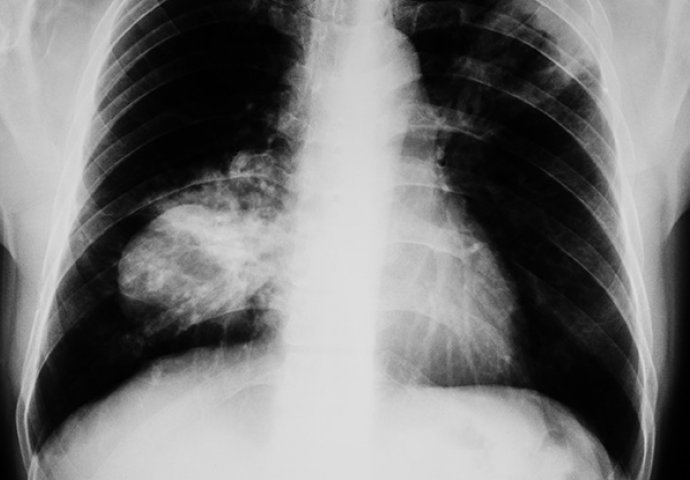

OTKRILA JE DA IMA RAK NA PLUĆIMA, SADA UPOZORAVA SVE: Ovo na rukama, nikad nemojte zanemariti!

Džin je radila testove krvi, skeniranja i rendgenske snimke prije nego što su doktori shvatili da se bori sa rakom pluća. Nakon uspostavljanja dijagnoze, Džin je otkrila znak upozorenja koji nikada ne smete zanemarivati. Krivljenje i savijanje noktiju, može biti indikator kancera.

‘Prije dvije sedmice, okačila sam na Fejsbuk fotografije, pitajući da li je neko nekada vidio takve nokte. Kasnije me je nekoliko prijatelja posavjetovalo da odem kod ljekara. Tada sam mislila da nije ništa ozbiljno. Nakon dvije naporne sedmice, jučer sam dobila svoje rezultate … Imam rak pluća. – napisala je Džin.